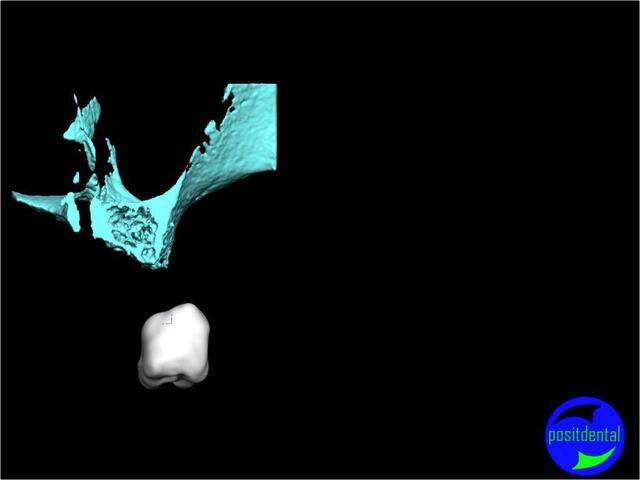

Posit fait une étude pour démontrer la faisabilité de son système, et honnêtement sa démarche semble intéressante, et provoque une réflexion sympa chez D57 et moi même.

La solution unique n'existant pas il est très intéressante que nous échangions nos différents points de vue.

La solution sera une expansion, (what else?) mais dirigée du point de vue prothésiste pour la partie mécanique, ce qui devrait être plus sécurisant pour le patient, et constructif pour nous tous.

une autre vue du photshopman:

modèle stéréo du à la gentillesse de Posit